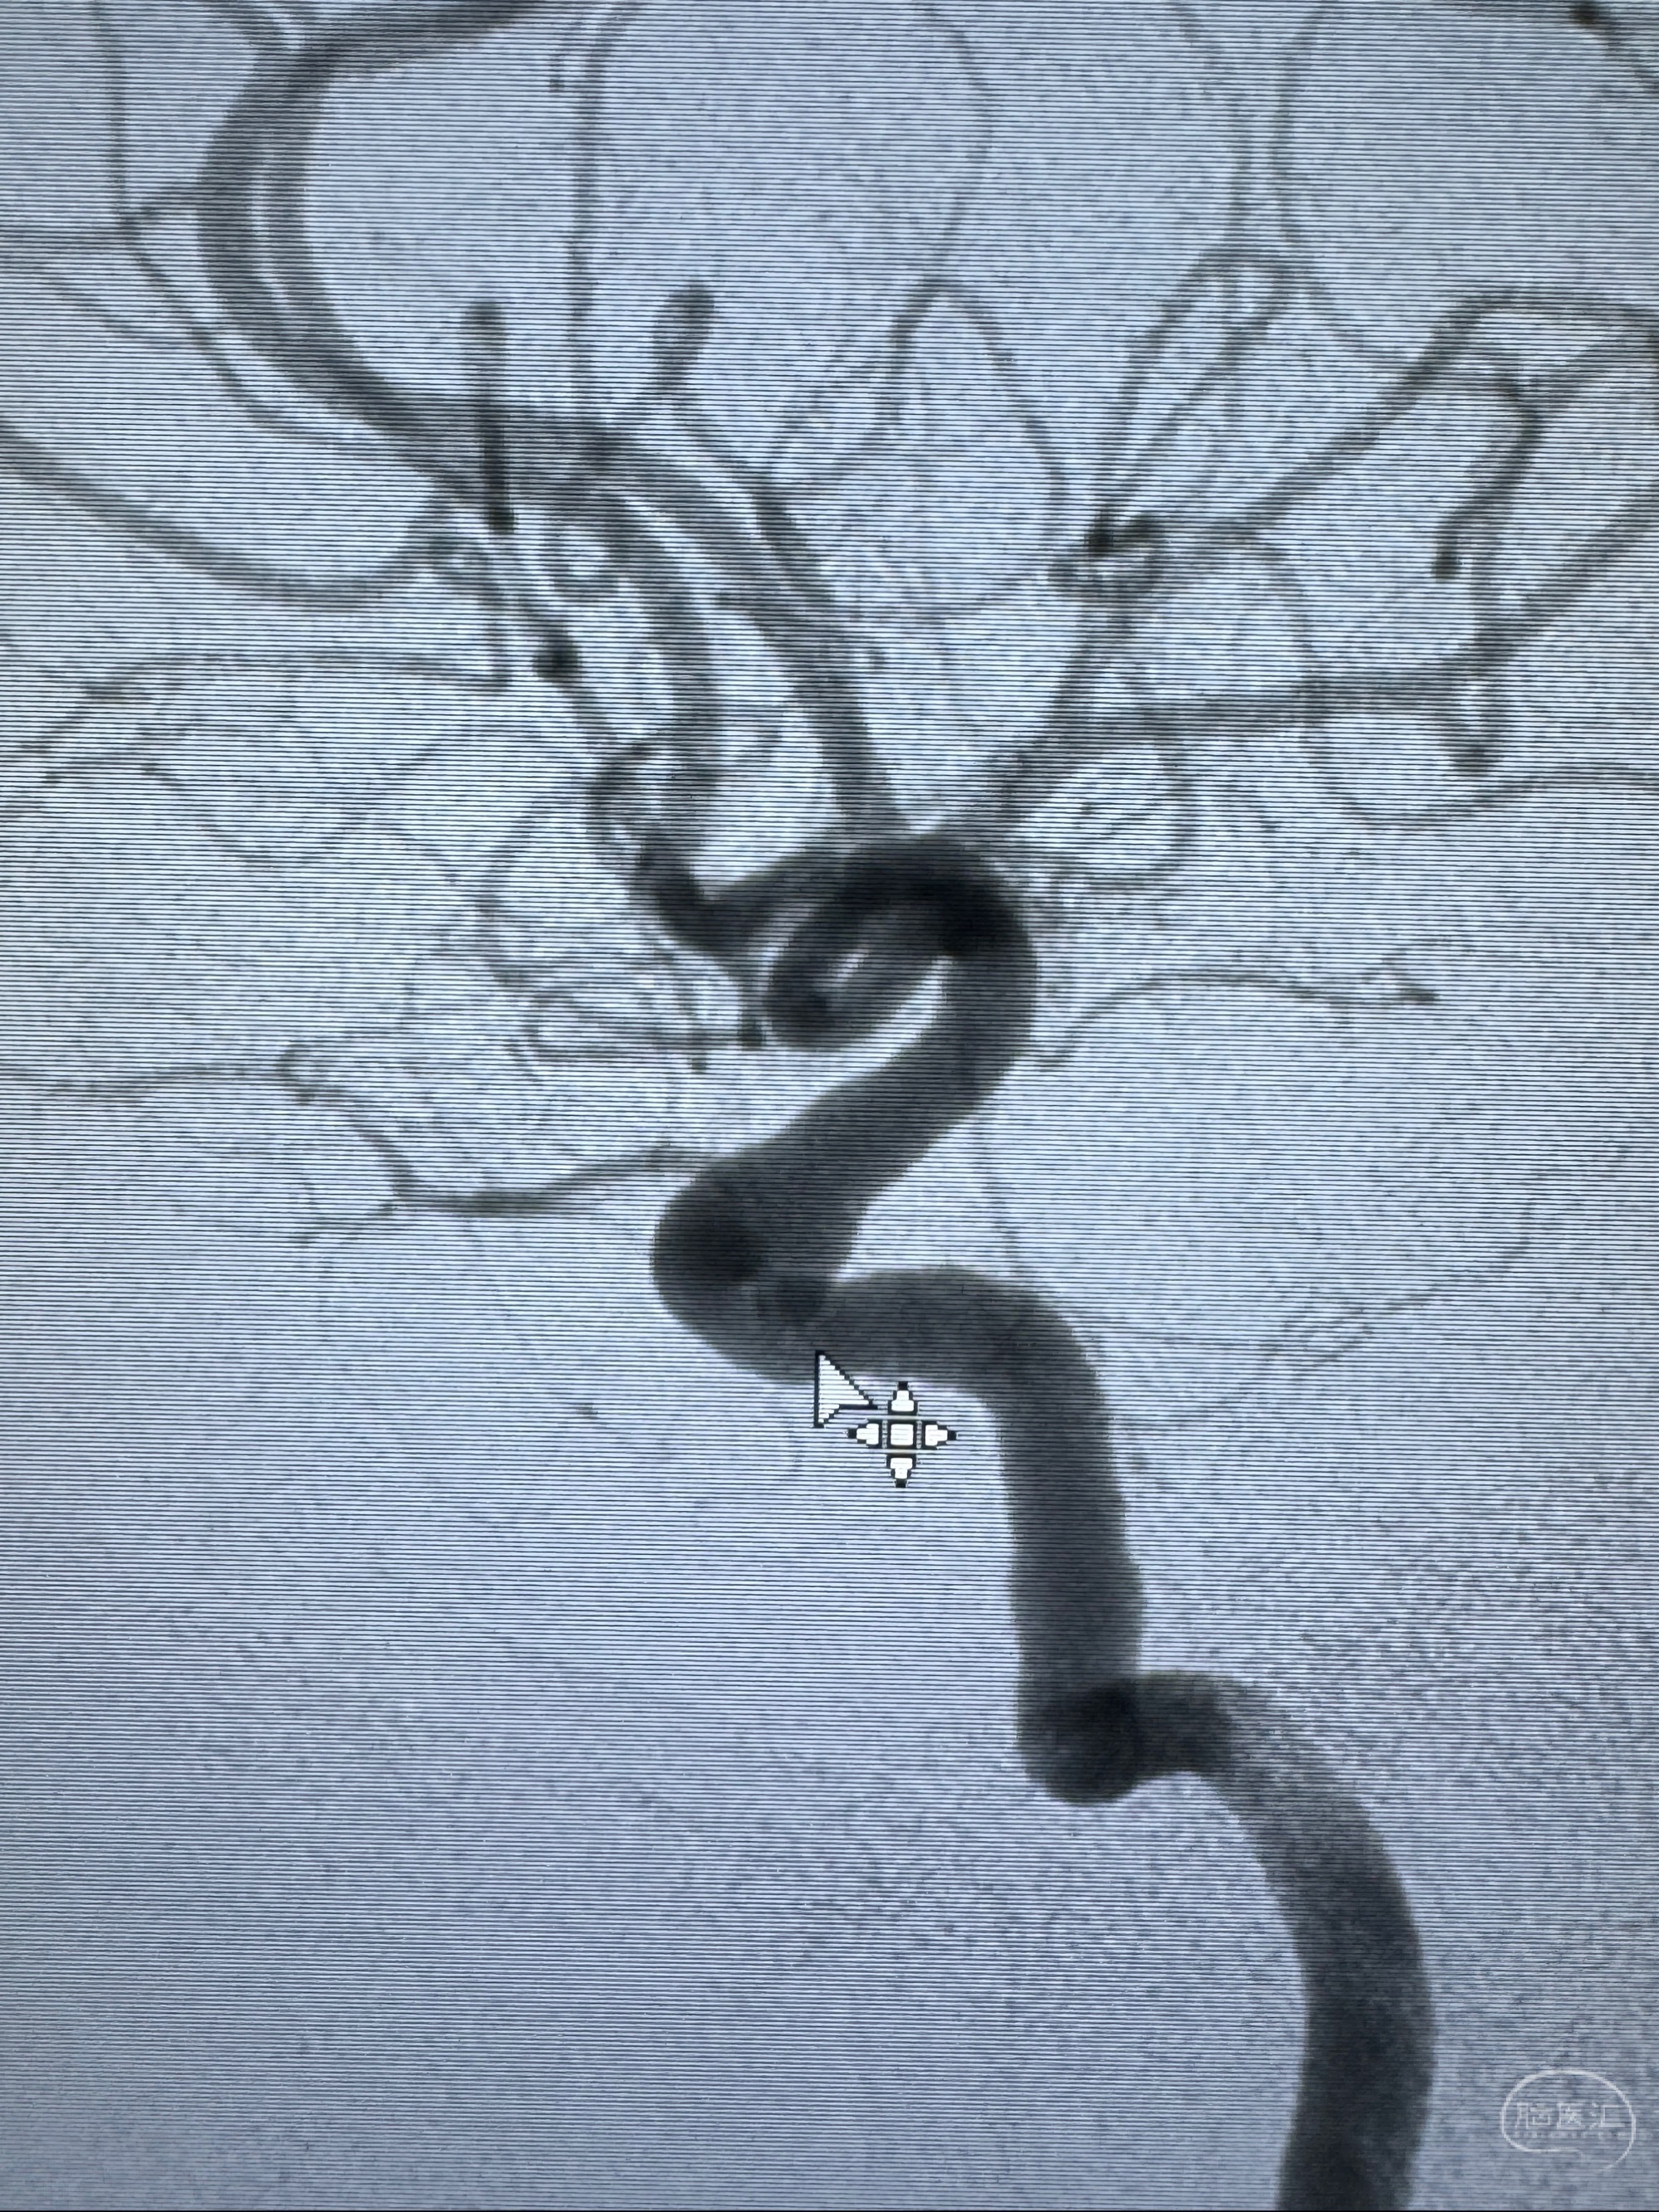

现病史:患者诉近4年来时有头痛发作,服用都梁软胶囊、氟桂利嗪对症治疗一月后症状改善,后头痛较少发作。近3月来患者头痛发作频率明显增加,约一月一次,为右侧偏头痛,胀痛,伴恶心呕吐,呕吐后症状可略减轻;遂于2023-11-01至蓝十字脑科医院就诊,查头颅MRI+DWI+MRA提示:左侧枕叶皮层下小斑片缺血或变性灶,右侧大脑前动脉A1段毛糙,显影淡、纤细,建议完善CTA;并于2023-11-03查头颅CTA提示:左侧颈内动脉C6段微小动脉瘤可能(约2mm),右侧大脑前动脉A1段纤细(对侧优势),左侧大脑中动脉提前分叉。现患者无明显不适,为求进一步诊疗颅内血管病变至我科就诊,收治入院。

2023-11-03 蓝十字脑科医院 头颅CTA:左侧颈内动脉C6段微小动脉瘤可能(约2mm),右侧大脑前动脉A1段纤细(对侧优势),左侧大脑中动脉提前分叉。

1.左侧颈内动脉瘤